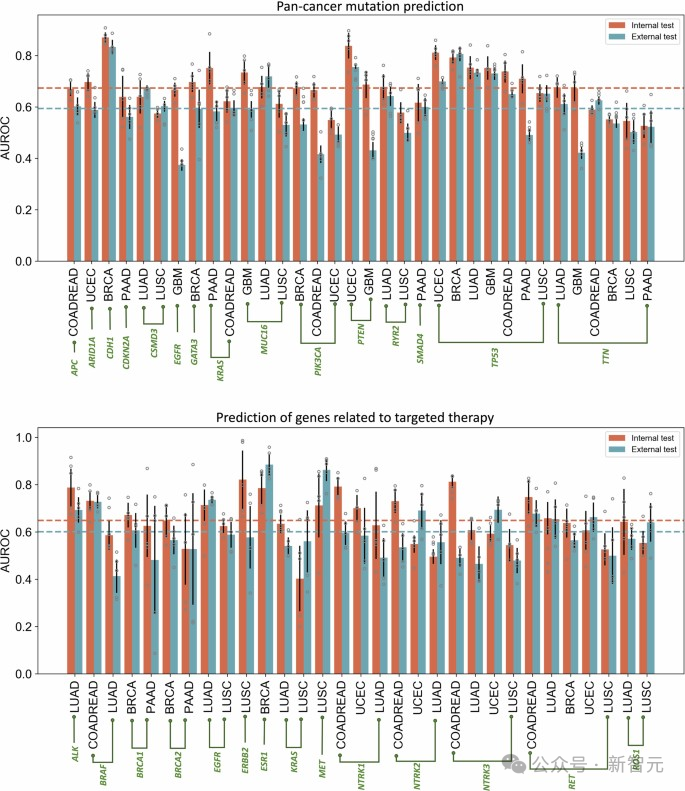

CHIEF在预测肿瘤的基因变异方面优于现有的AI方法。这种新的AI方法成功识别了与癌症生长和抑制相关的多个重要基因特征,并预测了肿瘤在各种标准癌症疗法过程中的关键基因突变。

在观察全组织图像时,CHIEF识别出54个常见突变癌症基因中的突变,总体准确率超过70%,优于当前用于基因组癌症预测的最先进AI方法。

研究团队使用CHIEF模型来预测特定基因突变,这些突变与FDA(美国食品药品监督管理局)批准的靶向治疗方法的效果有关。研究涉及的18个基因分布在人体的15个不同解剖部位。

CHIEF在多种癌症类型中都达到了高准确率。在检测一种名为弥漫性大B细胞淋巴瘤的血液癌症中的EZH2基因突变时,CHIEF达到了96%的准确率;在检测甲状腺癌中的BRAF基因突变时,CHIEF的准确率达到了89%;在检测头颈部癌症中的NTRK1基因突变时,准确率为91%。

CHIEF 在预测癌症类型的组织病理学图像中的基因突变状态方面取得了很高的成绩